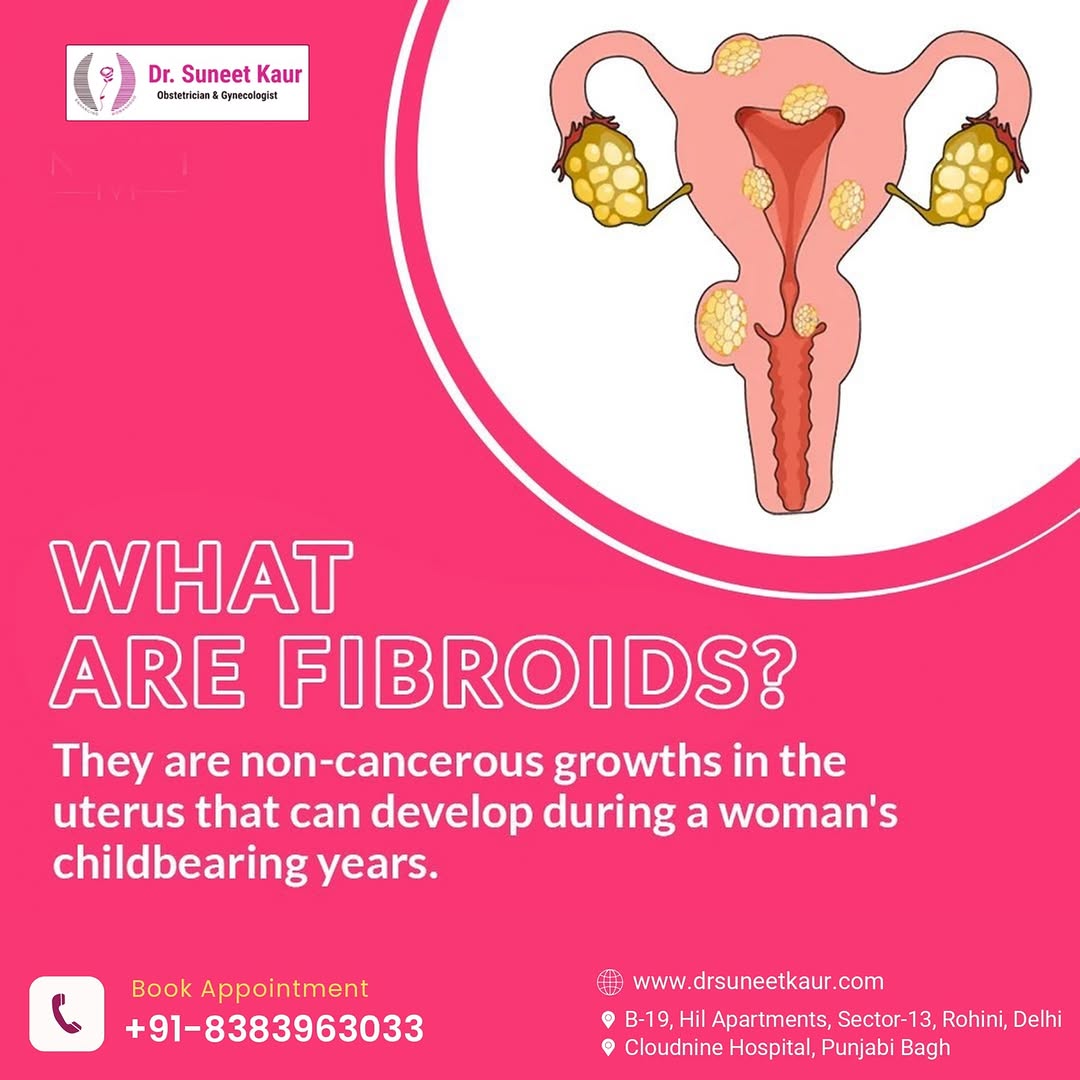

Uterine Fibroids

Non-invasive and surgical treatment options for fibroids causing heavy bleeding, pain, infertility, or pressure symptoms.

- Fibroid Uterus Treatment

Diagnosis and treatment for menstrual issues, PCOS, menopause, infections, fibroids, and pelvic pain.

Minimally invasive solutions for fibroids, ovarian cysts, ectopic pregnancy, and hysterectomy with faster healing.